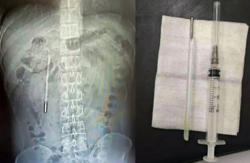

Termometer yang berjaya dikeluarkan daripada duodenum lelaki berkenaan. -Foto Weibo/SCMP

Hasil pemeriksaan imbasan mendapati terdapat objek asing di bahagian duodenum (bahagian pertama usus kecil) lelaki berkenaan.

Lebih mengejutkan, doktor mengesyaki objek tersebut ialah termometer merkuri.

Menurut doktor, keadaan itu berisiko tinggi kerana hujung termometer berkenaan menekan terus ke dinding usus, sekali gus boleh menyebabkan kebocoran dan pendarahan dalaman yang serius.

Pasukan pakar bedah berjaya mengeluarkan objek berkenaan dalam tempoh kira-kira 20 minit menerusi prosedur khas.

Bagaimanapun, pembedahan itu dianggap rumit dan berisiko tinggi memandangkan termometer tersebut telah berada lama dalam tubuh serta terletak berhampiran saluran hempedu, yang boleh menyebabkan kerosakan pada dinding usus.

Selepas dikeluarkan, termometer itu didapati masih dalam keadaan utuh, namun tanda ukurannya sudah pudar.